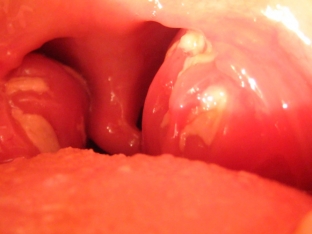

The salivary glands, lymph nodes, and tonsils are the first organs to become infected with the virus.

In addition, the development of EBV in children can be the cause of not only enlarged lymph nodes, the development of lymphadenopathy or lymphadenitis, but also permanent tonsillitis.

If the Epstein-Barr virus in children occurs in the form of infectious mononucleosis, the characteristic symptoms may be: vomiting, soreness in the abdomen, rare stools, pneumonia, swollen lymph nodes, weakness and headache.

A child who has recovered from mononucleosis may experience enlarged lymph nodes and problems with the liver, kidneys and spleen for a year and a half, tonsillitis and pharyngitis may occur.